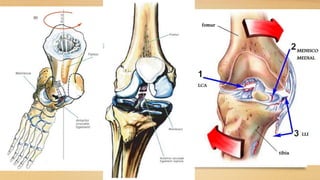

ANATOMIA

Meniscos se desplazan hacia

posterior en la flexion, en la

extensión están en su sitio

Durante la extensión, el

compartimento externo es el

primero en alcanzar la extensión

completa, al ser la extensión

completa se da un mecanismo de

rosca al rotar internamente el femur

sobre la tibia, bloqueando la rodilla